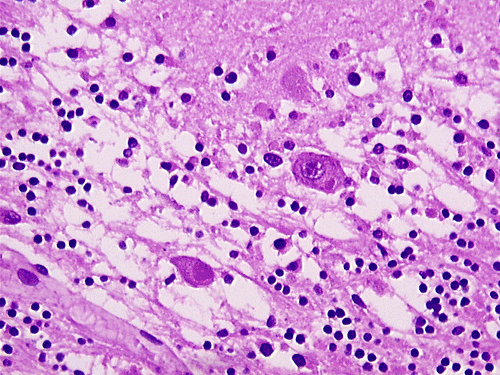

The overall tissue preservation is less than optimal because of postmortem autolysis. Panel A and B are taken from the cerebellum. The molecular layer, Purkinje cell layer, and internal granular layer are included (Panel A). Solitary eosinophilic intracytoplasmic inclusions of variable size are present in the Purkinje cells. No inflammatory cell infiltration is present in the cerebellum. The vacuolar spaces (Panel B) is partly due to autolysis and partly due to hypoxic/ischemic changes. Pyramidal cells in the hippocampus (Panel C), cortical neurons in parietal lobe (Panel D) and other neocortical areas adopted an elongated and contracted contour with loss of nuclear details. These are histologic features consistent with hypoxic/ischemic changes. Similar to the cerebellum, solitary eosinophilic cytoplasmic inclusion bodies are present and there is no inflammatory cell infiltration. Multiple eosinophilic cytoplasmic inclusion bodies within a single neuron are occasionally found. Some of these neurons containing multiple inclusions from the substantia nigra are illustrated in Panel E. Although inflammatory cell infiltration is scant in the cerebrum and cerebellum, perivascular chronic inflammatory cell infiltrations are common in the medulla (Panel F and G), in the paravertebral sympathetic ganglion (Panel H and I) and in the spinal cord (not shown). Intracytoplasmic inclusions, however, are not found in the medulla, spinal cord, and paravertebral sympathetic ganglion. Under the electron microscope, rod-shape or bullet-shaped viral particles are found (Panel J).

The brain and spinal cord may appear swollen but are usually free of focal lesions. Histopathologically, rabies is a widespread polioencephalomyelitis. Leptomeningeal and parenchymal perivascular lymphocytic infiltrations are usually present but often not intense. Neuronophagia can also be seen. The amount of inflammation of the case under discussion is, in fact, on the intense side of the scale. The pathognomonic Negri bodies 10, 11, 12 are sharply delineated, round to oval, eosinophilic, neuronal cytoplasmic inclusions; first described by Negri in 1903 10. These inclusions are often solitary but may also be multiple in a single neuron. Lyssa bodies refer to less well delineated and more pleomorphic neuronal cytoplasmic viral inclusions. Babes’ nodules refer to clusters of microglia that remain after destruction of neurons. When immunohistochemistry is employed, the distributions of viral antigen are far more extensive than that estimated by conventional light microscopy 13. Negri body and rabies viral antigen as demonstrated by immunohistochemistry are most commonly seen in large neurons of the hippocampus (Pyramidal cells), cerebellum (Purkinje cells), thalamus, basal ganglia, cerebral cortex and in the brain stem, especially gray matter of the pons and medulla. They are also found in spinal cord motor neurons and dorsal root ganglion, especially in the paralytic form.  Immunohistochemistry also demonstrated rabies viral antigen in astrocytes and oligodendrocytes 13. Characteristically, a striking discrepancy between the degree of inflammation and amount of inclusion bodies is observed, as in our case, in many cases.